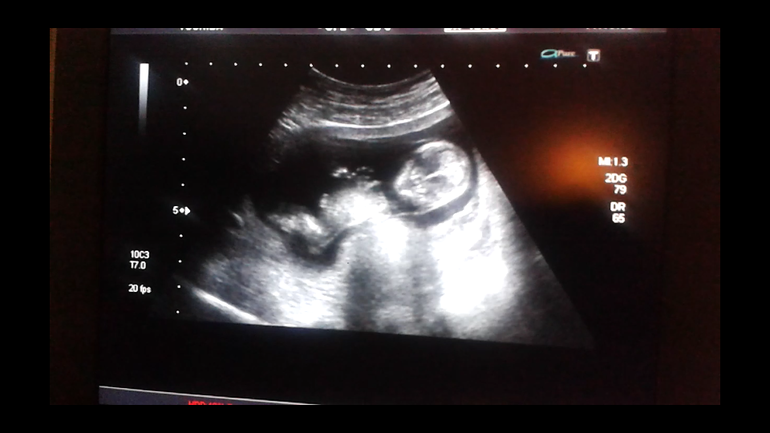

А что все ужи только снизу??? Может на видео есть боковой ракурс.

Вот моя доча вчера, поищите такой ракурс. У нас большой бугорок, но он параллельно позвоночника идёт.

Там у обоих полов точит на таком сроке! Потом у девочек исчезает! Он либо вверх направлен либо вниз. От этого зависит мальчик или девочка)